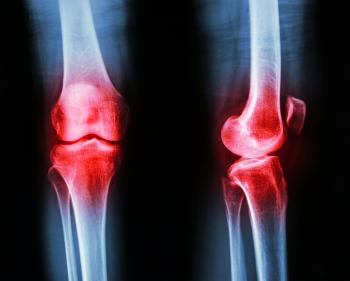

Perubahan yang besar ialah permukaan rawan yang licin itu menjadi lembut dan berlubangxx serta berbulu. Mulaxx selxx itu bole dibaiki tapi lamaxx proses tu gagal.

Bahagianxx besar rawan itu akan terhakis sepenuhnya dan ini mendedahkan hujungxx tulang tanpa perlindungan..